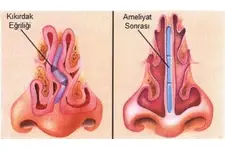

Fibröz kıkırdak, genellikle eklemlerde, disklerde ve tendonlarda bulunur. Özellikle omurgada intervertebral disklerde ve bazı eklemlerde önemli bir rol oynar. Fibröz Kıkırdağın Fonksiyonları Fibröz kıkırdak, vücutta birçok önemli işlevi yerine getirir:

Fibröz kıkırdak, travma veya aşınma sonucu zarar görebilir. Bu tür durumlarda, kıkırdak onarım süreçleri yavaş ilerleyebilir ve genellikle cerrahi müdahale gerektirebilir. Fibröz Kıkırdak Hastalıkları Fibröz kıkırdak ile ilişkili bazı hastalıklar ve durumlar şunlardır:

Bu hastalıkların tedavisi genellikle fizik tedavi, ilaç tedavisi ve cerrahi yöntemleri içerir. Sonuç Fibröz kıkırdak, vücudun destek ve hareket sisteminde kritik bir rol oynamaktadır. Yapı ve fonksiyon özellikleri sayesinde, çeşitli anatomik yapılar içinde önemli işlevler üstlenir. Fibröz kıkırdağın sağlığını korumak, genel fiziksel sağlık açısından önemlidir. Beslenme, egzersiz ve uygun tedavi yöntemleri ile fibröz kıkırdak sağlığı desteklenebilir. Ekstra Bilgiler Fibröz kıkırdağın onarım süreçleri, yaşla beraber yavaşlayabilir. Bu nedenle, yaşlanma sürecinde eklem sağlığını korumak için düzenli egzersiz yapmak ve sağlıklı beslenmek oldukça önemlidir. Ayrıca, fibröz kıkırdak sağlığını korumak için anti-inflamatuar besinlerin tüketilmesi önerilmektedir. Omega-3 yağ asitleri ve antioksidanlar bu bağlamda faydalı olabilir. Fibröz kıkırdak ile ilgili araştırmalar, bu dokunun onarım ve rejenerasyon potansiyelini artırma yönünde devam etmektedir. Gelecekte, biyomühendislik ve hücresel tedavi yöntemleri ile fibröz kıkırdağın onarımını sağlamak mümkün hale gelebilir. |